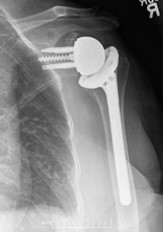

If the stability muscles of the shoulder are badly damaged, though, this traditional strategy might not work. RTSA reverses the positions of the ball and socket, allowing other muscles like the Deltoid muscles to compensate for the strength and mobility of the shoulder (Figure 2)

Figure 2: X-ray of a Reverse Total Shoulder Arthroplasty implant (KChri75,CC BY-SA 4.0, https://creativecommons.org/licenses/by-sa/4.0, via Wikimedia Commons)